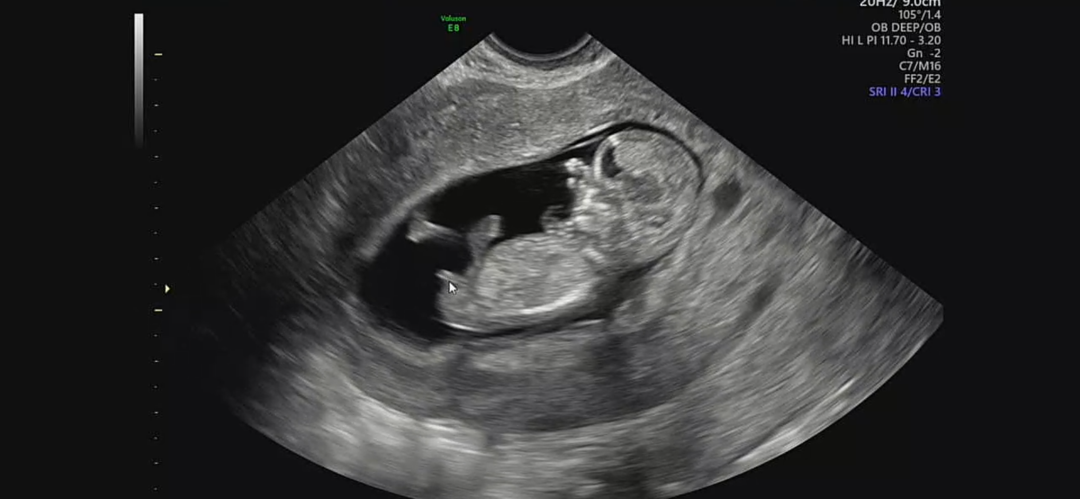

11주 3일인데 다리 사이에 뙇 보이는 생식기를 보고 제가 어 고추? 이랬는데 원장샘께서는 이 시기에는 아직 알 수 없다고 하셧거든요 각도법 고수님들 아들,딸 어떻게 될까요?

아들같아요!

저는 딸같은뎅

아들같아요 축하드립니다!!!